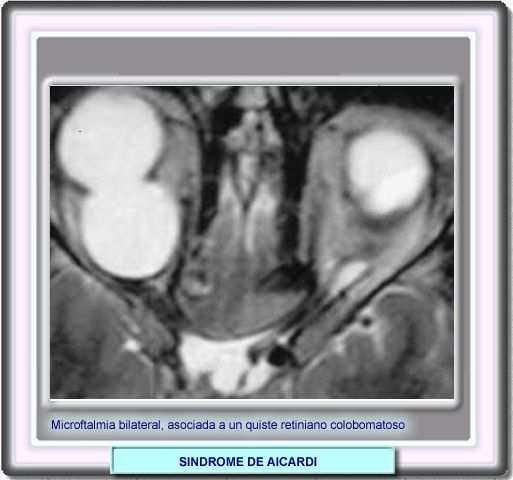

La microoftalmía bilateral y los quistes retinianos son hallazgos casi constantes del síndrome de Aicardi